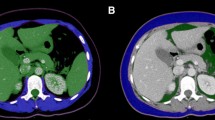

Skeletal muscle mass and fat tissues were measured using stored images from CT performed prior to any treatment, as previously described [7]. Skeletal muscles and visceral and subcutaneous fat areas were assessed from a single axial slice at the third lumbar (L3) level [14]. Hounsfield unit (HU)-based analysis of images was performed using dedicated SliceOMatic software (version 4.3; TomoVision, Montreal, Canada) to segment fat and lean tissue and quantify the cross-sectional area of each tissue type by totaling the given pixels of a tissue and multiplying that sum by the absolute unit pixel surface area (Supplemental Fig. 1). The following parameters were assessed: skeletal muscle mass including the mass of the psoas, quadratus lumborum, transversus abdominis, external and internal obliques, rectus abdominis, and erector spinae muscles; subcutaneous fat mass including the fat present in the subcutaneous tissue; and intramuscular fat contained in intercostal muscles and visceral fat mass. The fat present in the psoas was not considered for the assessment of adiposity. CT attenuation thresholds were − 29 HU to 150 HU for skeletal muscles and − 190 HU to − 30 HU and − 50 HU to − 150 HU for subcutaneous and visceral adipose tissues, respectively. Adipose tissue was taken as the sum of subcutaneous and visceral adipose tissues. This value was normalized for stature to calculate the lumbar L3 skeletal muscle index (SMI) and lumbar L3 adipose tissue index (ATI).

Clinical characteristics of the 90 patients examined in this study are summarized in Table 1. The study population comprised 51 males and 39 females. Median age at diagnosis was 59 years (range, 18–84 years). Thirty patients were classified as showing favorable cytogenetic risk, while 46 showed intermediate risk and 12 showed adverse risk. Cytogenetic risk was unknown in two patients. Sixty-five patients (72%) received intensive chemotherapy, and 25 patients (28%) received reduced intensity chemotherapy as induction therapy. Median SMI was 42.5 cm2/m2 (range, 26.8–61.8 cm2/m2) and median ATI was 73.9 cm2/m2 (range, 2.1–188.9 cm2/m2). SMI was significantly higher in males than in females (P < 0.0001), whereas no difference in ATI was seen between males and females (P = 0.96). The cutoff SMI used to identify sarcopenia was defined as < 48.4 cm2/m2 in males and < 33.5 cm2/m2 in females. The cutoff ATI used to identify adipopenia was defined as < 63.5 cm2/m2 in males and < 46.0 cm2/m2 in females. Thirty-nine patients (43%) showed sarcopenia, and 35 patients (39%) showed adipopenia. According to performance status (PS), 39% of patients with PS ≤ 1 showed sarcopenia, compared to 67% of patients with PS ≥ 2 (P < 0.05). Fat mass was significantly lower in patients < 60 years old than in elderly patients (Table 1). No correlation was evident between the value of serum albumin and either SMI or ATI. The presence or absence of comorbidity before treatment was unrelated to sarcopenia (data not shown).